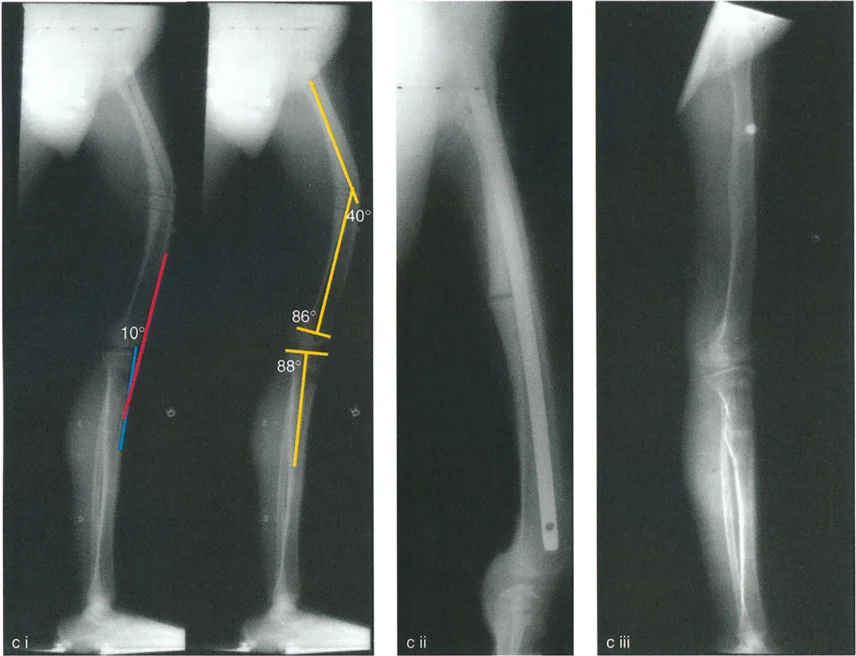

- حالة مريضة تبلغ من العمر 24 عامًا عانت من كسر في الفخذ في سن 12 عامًا، وعولجت بالشد. تسبب دبوس الشد في توقف نمو جزئي في الجزء القريب من عظم الساق، مما أدى إلى ارتداد ظنبوبي.

- تقييم مدى الحركة: يتم قياس مدى حركة الركبة، بما في ذلك أقصى تمدد وأقصى انثناء. يتم تحديد درجة فرط التمدد (HE - Hyperextension) أو درجة تقلص الانثناء الثابت (FFD - Fixed Flexion Deformity).

زوايا القياس الهامة:

- زاوية الانحناء البعيدة للفخذ (PDFA - Posterior Distal Femoral Angle): تقيس زاوية الجزء السفلي من عظم الفخذ. القيمة الطبيعية حوالي 84 درجة. الزيادة في هذه الزاوية (أكثر من 84 درجة) تشير إلى ارتداد فخذي.

- زاوية الانحناء القريبة للظنبوب (PPTA - Proximal Posterior Tibial Angle): تقيس زاوية الجزء العلوي من عظم الساق. القيمة الطبيعية حوالي 80 درجة. الزيادة في هذه الزاوية (أكثر من 80 درجة) تشير إلى ارتداد ظنبوبي.

- مركز دوران الزاوية (CORA - Center of Rotation of Angulation): يتم تحديد هذا النقطة على الأشعة السينية لتحديد مكان التشوه العظمي بدقة، وهو أمر بالغ الأهمية لتخطيط عملية قطع العظم.

تحليل الحالات المختلفة:

- الركبة الارتدادية بسبب الارتداد الفخذي:

- إذا كانت درجة فرط التمدد (HE) تساوي درجة الارتداد الفخذي (PDFA > 84°)، فهذا يعني أن التشوه كله ناتج عن عظم الفخذ.

- في هذه الحالة، يكون مركز CORA في الجزء البعيد من عظم الفخذ.

- الركبة الارتدادية بسبب الارتداد الظنبوبي:

- إذا كانت درجة فرط التمدد (HE) تساوي درجة الارتداد الظنبوبي (PPTA > 80°)، فهذا يعني أن التشوه كله ناتج عن عظم الساق.

- في هذه الحالة، يكون مركز CORA في الجزء القريب من عظم الساق.

- الركبة الارتدادية بسبب تشوه مركب (فخذي وظنبوبي):

- إذا كان هناك ارتداد في كل من الفخذ والساق، وكان مجموع درجتي الارتداد يساوي درجة فرط التمدد الكلي للركبة.